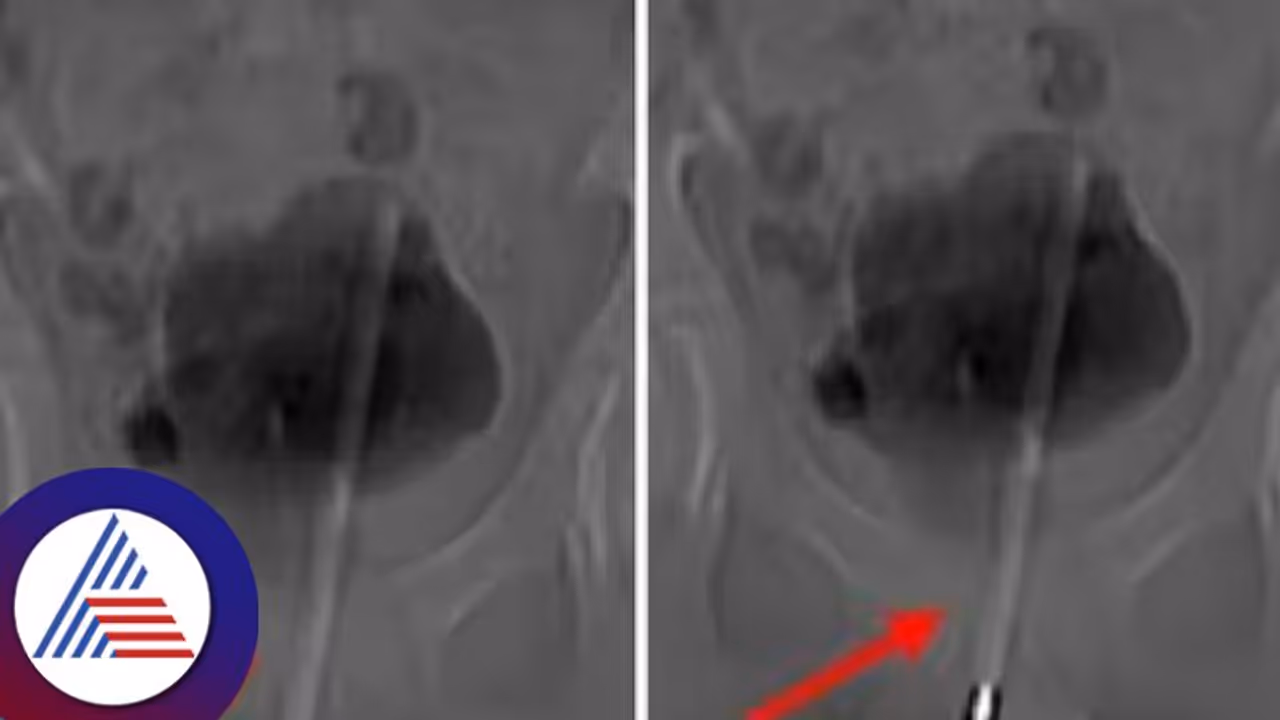

12 ವರ್ಷದ ಬಾಲಕನ ಮೂತ್ರಕೋಶದಿಂದ ವೈದ್ಯರು ಥರ್ಮೋಮೀಟರ್ನ್ನು ತೆಗೆದುಹಾಕಿದ್ದಾರೆ. ಸುದೀರ್ಘ ಶಸ್ತ್ರಚಿಕಿತ್ಸೆಯ ಮೂಲಕ ವೈದ್ಯರು 12 ವರ್ಷದ ಮಗುವಿನ ಮೂತ್ರಕೋಶದಿಂದ ಥರ್ಮೋಮೀಟರ್ನ್ನು ತೆಗೆದುಹಾಕಿದ್ದಾರೆ. ಹಸ್ತಮೈಥುನದ ಸಮಯದಲ್ಲಿ ಥರ್ಮೋಮೀಟರ್ ಶಿಶ್ನವನ್ನು ಪ್ರವೇಶಿಸಿರಬಹುದು ಎಂದು ವೈದ್ಯರು ಹೇಳಿದ್ದಾರೆ. ಒಂಬತ್ತು ಗಂಟೆಗಳ ಕಾಲ ತೀವ್ರ ನೋವಿನಿಂದ ಬಳಲುತ್ತಿದ್ದ ಮಗುವನ್ನು ಆಸ್ಪತ್ರೆಗೆ ದಾಖಲಿಸಲಾಗಿತ್ತು. ಥರ್ಮೋಮೀಟರ್ ಮೂತ್ರನಾಳವನ್ನು ಪ್ರವೇಶಿಸಿ ಮಗುವಿನ ಮೂತ್ರಕೋಶವನ್ನು ಪ್ರವೇಶಿಸಿದೆ ಎಂದು ಎಕ್ಸ್-ರೇಗಳು ಬಹಿರಂಗಪಡಿಸಿದವು. ಕೀ ಹೋಲ್ ಸರ್ಜರಿ ಮೂಲಕ ಮಗುವಿನ ಮೂತ್ರಕೋಶದಿಂದ ಥರ್ಮಾಮೀಟರ್ ಹೊರತೆಗೆಯಲಾಗಿದೆ ಎಂದು ಆಪರೇಷನ್ ನಡೆಸಿದ ವೈದ್ಯರು ತಿಳಿಸಿದ್ದಾರೆ.

ವೈದ್ಯರನ್ನು ಮೂತ್ರವನ್ನು ಸಂಗ್ರಹಿಸಿದ ಮೂತ್ರಕೋಶಕ್ಕೆ ಅಂಗಾಂಶದಲ್ಲಿ ಸಣ್ಣ ಶಸ್ತ್ರಚಿಕಿತ್ಸೆಯ ರಂಧ್ರವನ್ನು ಮಾಡಿದರು ಮತ್ತು ನಂತರ ಥರ್ಮಾಮೀಟರ್ ಅನ್ನು ಸರಿಯಾದ ಕೋನ ಮತ್ತು ಸ್ಥಾನಕ್ಕೆ ಕುಶಲತೆಯಿಂದ ನಿರ್ವಹಿಸಲು ಸಣ್ಣ ಉಪಕರಣಗಳನ್ನು ಸೇರಿಸಿದರು ಮತ್ತು ನಂತರ ಅದನ್ನು ಕೀ-ಹೋಲ್ ಮೂಲಕ ಹೊರತೆಗೆದರು. ಡಾ. ಚಾಂಗ್ಸಿಂಗ್ ಕೆ, 'ಲೈಂಗಿಕ ಶಿಕ್ಷಣದ (Sex Education) ಕೊರತೆ ಮತ್ತು ಕುತೂಹಲದ ಪರಿಣಾಮವಾಗಿ, ಹಸ್ತಮೈಥುನಕ್ಕಾಗಿ ಮಗು ಥರ್ಮಾಮೀಟರ್ ಅನ್ನು ಶಿಶ್ನಕ್ಕೆ ಸೇರಿಸಿತು' ಎಂದು ಹೇಳಿದರು. ಕಳೆದ ಕೆಲವು ವರ್ಷಗಳಿಂದ ಯುಕೆಯಲ್ಲಿ ಈ ಸಮಸ್ಯೆಯಿಂದ ಬಳಲುತ್ತಿರುವ ಪುರುಷರ ಸಂಖ್ಯೆಯಲ್ಲಿ ಹೆಚ್ಚಳವಾಗಿದೆ ಎಂದು ತಜ್ಞರು ವರದಿ ಮಾಡಿದ್ದಾರೆ.